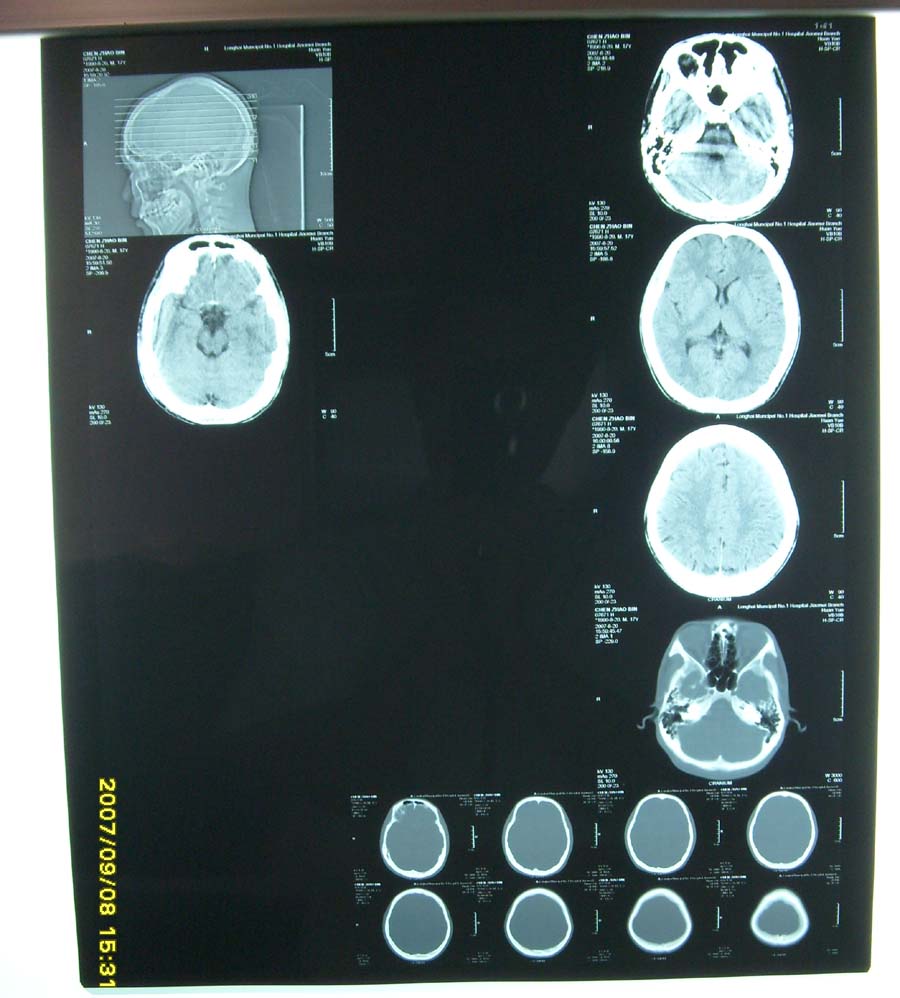

我医院使用的是西门子欢悦单排螺旋ct,打印机是柯达8150,为什么有时打印出来的图片是这样,再请问一个问题:为什么胶片盒还剩一张或二张胶片,而电脑屏幕却提示没有胶片呢,这样每次都要浪费一、二张胶片,有什么好办法能解决这个问题.请指教。